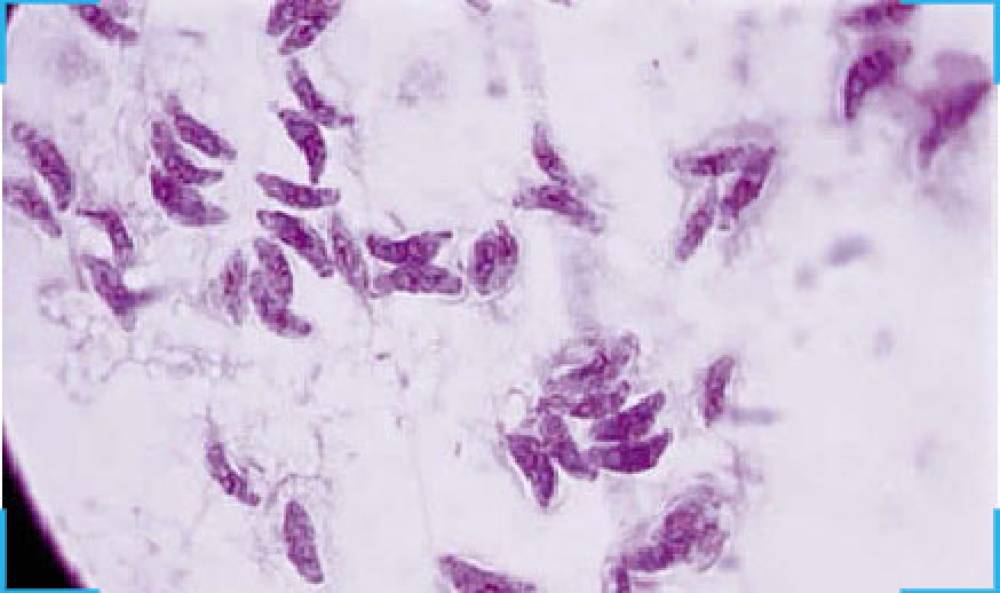

TRUPCR® Toxoplasma Detection Kit is an in vitro nucleic acid amplification assay for the qualitative detection of Toxoplasma spp using Real Time PCR System. Each test is a multiplex reaction with two independent reactions running in parallel in which one target is for Toxoplasma spp detection in Hex/Yellow channel and another one for internal control (IC) detection in Tex Red/orange channel.